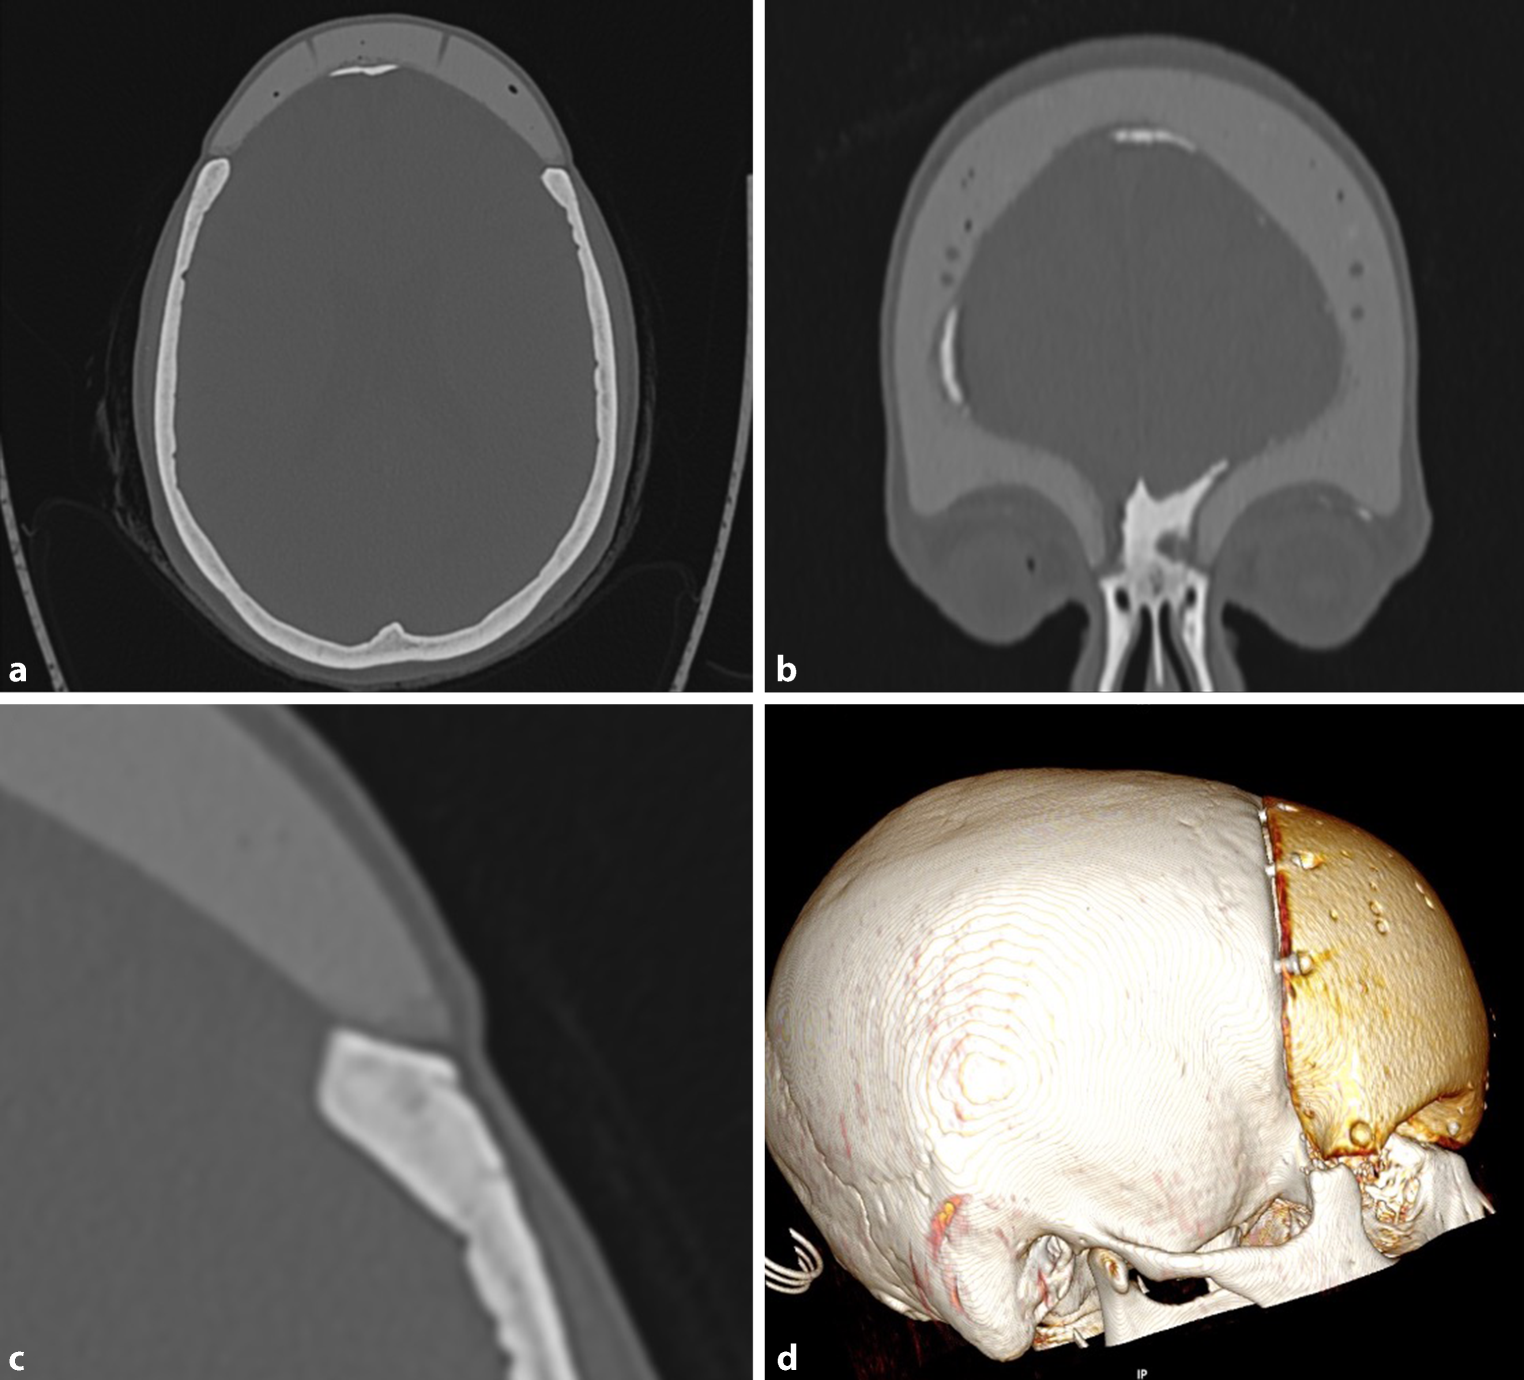

Fig. 2

CT scans of a carbon fiber-reinforced resin implant after resection of a fibrous dysplasia of the frontal bone, 22 years after implantation. a This scans show an Axial view, the calcification of adjacent dura, bore holes in the implant for suturing the dura to the implant. b Same patient in a Coronal view. c The axial view shows sufficient implant-bone contact. d 3‑D reconstructions shows the positioning of the screws

The dura showed calcification under the implant in 6 of 9 cases (Fig. 2).